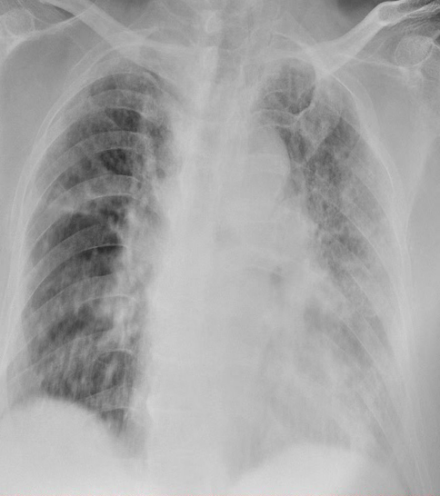

患者住院第五天,呼吸机参数已进入相对平稳期。此时,患者的驱动压及平台压均处于安全范围(表4);复查胸片显示肺部情况较之前逐步好转(图6)

图片

6  复查胸部X线片